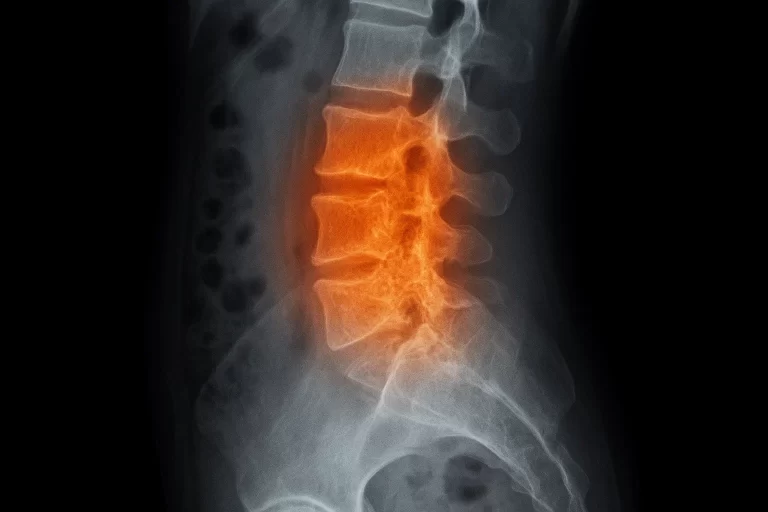

- Radiografía del cuello

- Tomografía computarizada del cuello (TAC)

- Electromiografía para comprobar los músculos afectados

- Resonancia magnética del cerebro

- Examen de sangre para buscar posibles afecciones asociadas a esta dolencia